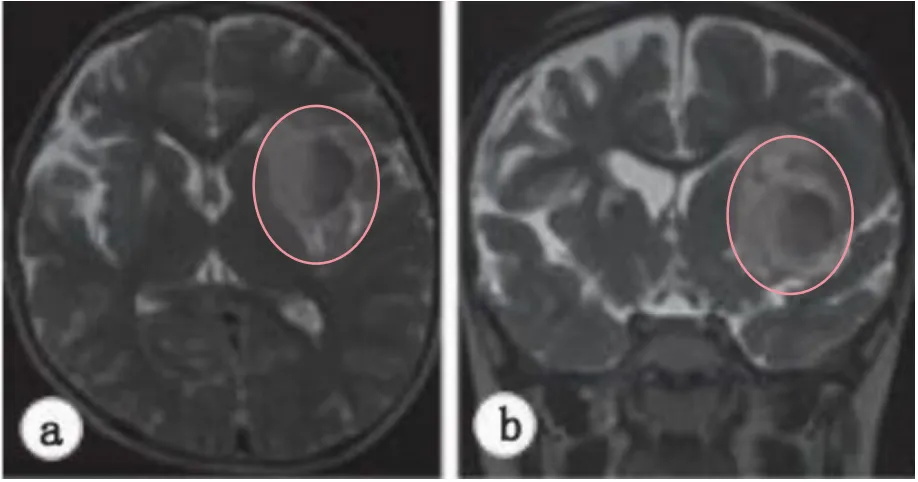

然而一个月后再行检查,发现病变已经扩大并压迫了周围的脑组织(图4a–c).尽管病变无症状,但预计病变还会进一步扩大,产生神经症状;经过商议,因此决定采用显微手术切除病变。

图4.二次术后随访MR发现,左侧岛叶病灶长大了两倍以上,明显水肿。

c术后MRI显示手术瘢痕组织,而不是术前异常肿块。